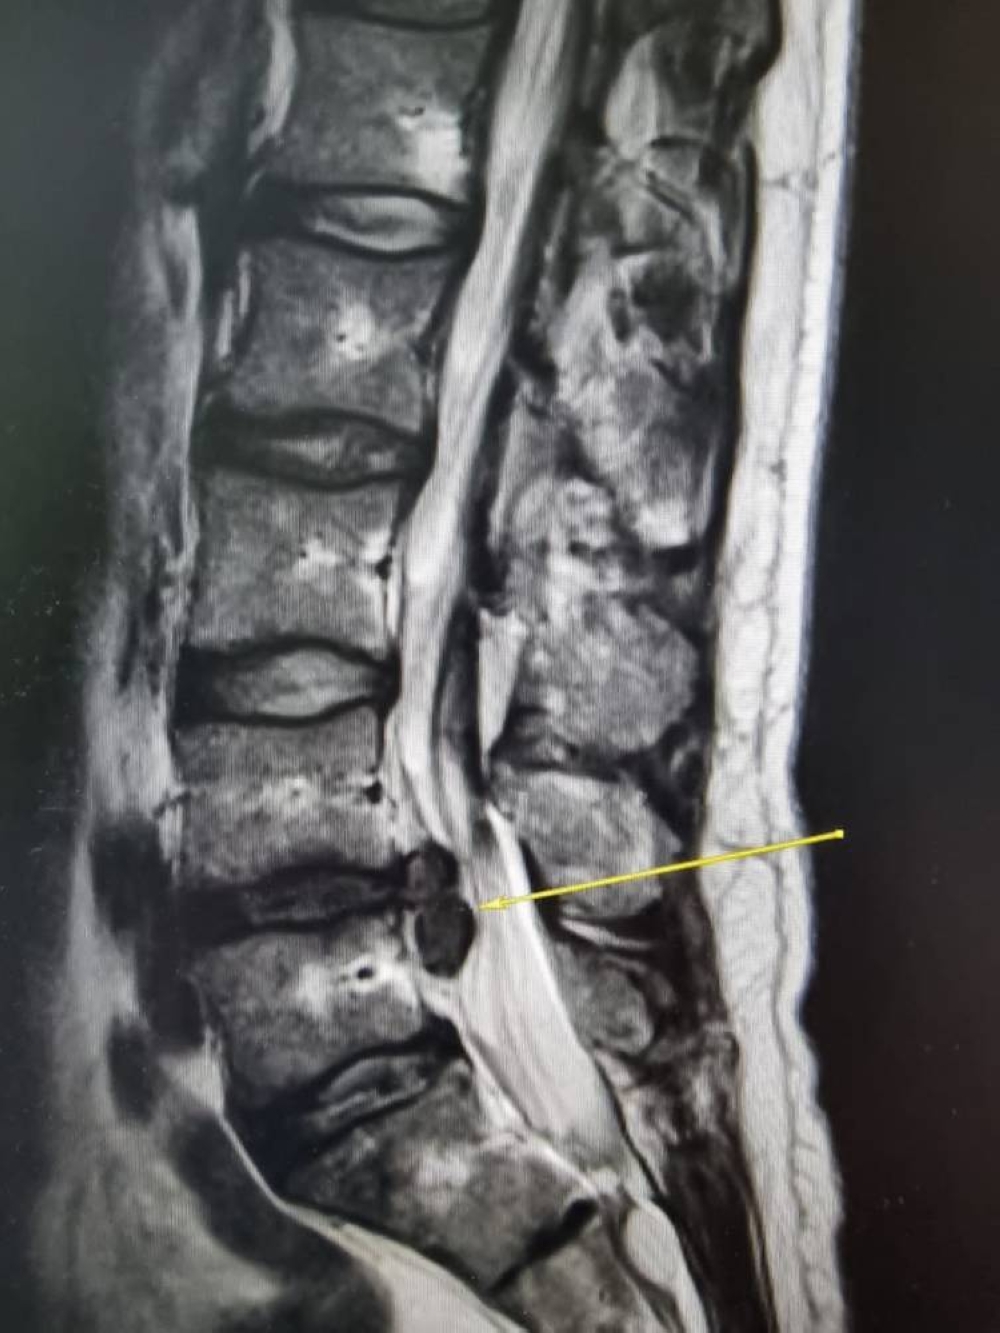

وأوضح استشاري جراحة العمود الفقري والمناظير الفقرية الدكتور ضاوي العتيبي، أن المريض كان يعاني من ضيق في القناة العصبية للفقرات القطنية مصاحبة ببروز للدسك؛ وكذلك دسك منفصل محشور أسفل مستوى الدسك بين الفقرتين الرابعة والخامسة ، سبب له ألم في الظهر وألم شديد في الطرف السفلي الأيمن "عرق النسا" وضعف في القدم اليمنى.

وأضاف د . ضاوي أن من ضمن تحديات الحالة وجود تشوهات خلقية في الفقرات، لافتاً إلى أن تقنية المنظار ثنائي المنافذ من جراحات الظهر الطفيفة والموجهة، حيث يتم إزالة التضييق في المستوى المتأثر دون الإضرار بالعضلات أو الأربطة المحيطة.